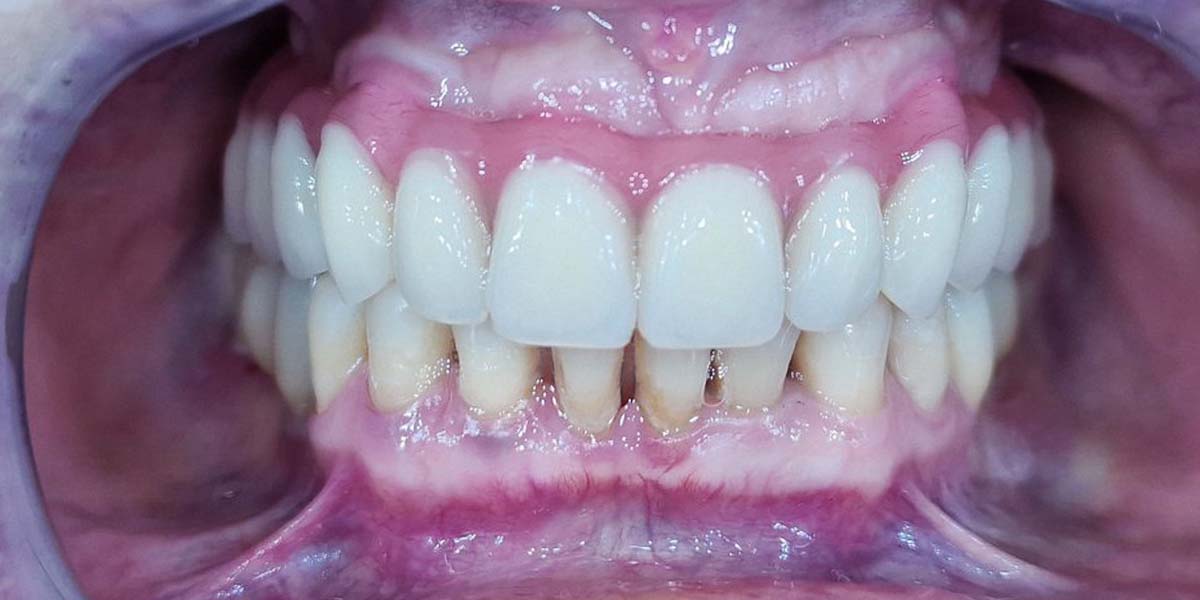

Praėjus gijimo laikotarpiui, pacientė pasirinko nuolatinį viso žandikaulio ant 5 impantų metalo-akrilo dantų protezą. Ponia liko patenkinta rezultatu, nes ir vėl gali plačiai šypsotis. Sugrįžus gyvenimo džiaugsmui, grįžo noras bendrauti. Tad dabar ponią galima sutikti tik puikios nuotaikos.

Procedūros buvo parinktos atsižvelgiant į pacientės burnos būklę ir dantų praradimo mastą. Implantacija ir individualiai pritaikytas protezas užtikrino ne tik estetinį rezultatą, bet ir funkcionalumą, suteikdami pacientės gyvenimui naują džiaugsmą bei galimybę vėl laisvai bendrauti. Po visų procedūrų pacientė liko patenkinta gauta paslauga ir sugrįžo į kasdienį gyvenimą, pilną šypsenų.